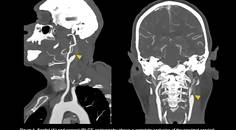

Ischemic Complications from a Facial Lipofilling Procedure

Sanaz Rezaei, MD; Fatemeh Talebi, MDSanaz Rezaei, MD; Fatemeh Talebi, MD - Stroke